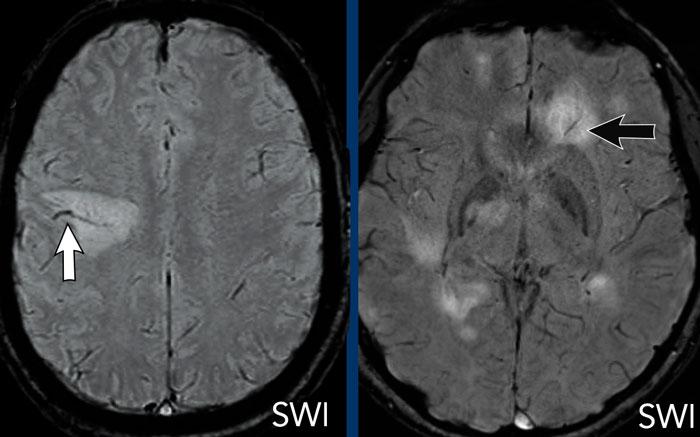

U lympho

Các hình ảnh này của một phụ nữ 76 tuổi, có biểu hiện lú lẫn sau khi ngã.

Hãy quan sát các hình ảnh trước rồi mới tiếp tục đọc.

Câu hỏi:

- Chẩn đoán có khả năng nhất là gì?

- Những dấu hiệu nào điển hình cho chẩn đoán này?

Các dấu hiệu bao gồm:

- Tổn thương tăng tỷ trọng trên CT không tiêm thuốc cản quang kèm phù não do mạch máu.

- MRI cho thấy nhiều tổn thương ngấm thuốc dạng đặc và hạn chế khuếch tán.

- Trên chuỗi xung T2W, các tổn thương biểu hiện giảm tín hiệu.

- Một tổn thương nằm ở thể chai và một tổn thương khác nằm cạnh não thất.

Tất cả các dấu hiệu này đều điển hình cho u lympho nguyên phát hệ thần kinh trung ương, khác với u lympho hệ thống.

Các khối u này chiếm 6-7% tổng số u hệ thần kinh trung ương và mô học là u lympho tế bào B không Hodgkin.

Chúng thường nằm ở vùng cạnh não thất dưới màng nội tủy, thể chai và hạch nền.

Luôn nghĩ đến u lympho khi gặp tổn thương ngấm thuốc dạng đặc nằm gần não thất.

Hình ảnh tăng tỷ trọng trên CT, giảm tín hiệu nhẹ trên chuỗi xung T2W cũng như hạn chế khuếch tán được giải thích là do mật độ tế bào dày đặc của mô u lympho.

Ở bệnh nhân suy giảm miễn dịch, kiểu ngấm thuốc có thể là dạng vòng nhẫn.

Bệnh nhân này có nhiều phù não, nhưng trong nhiều trường hợp phù não rất hạn chế.